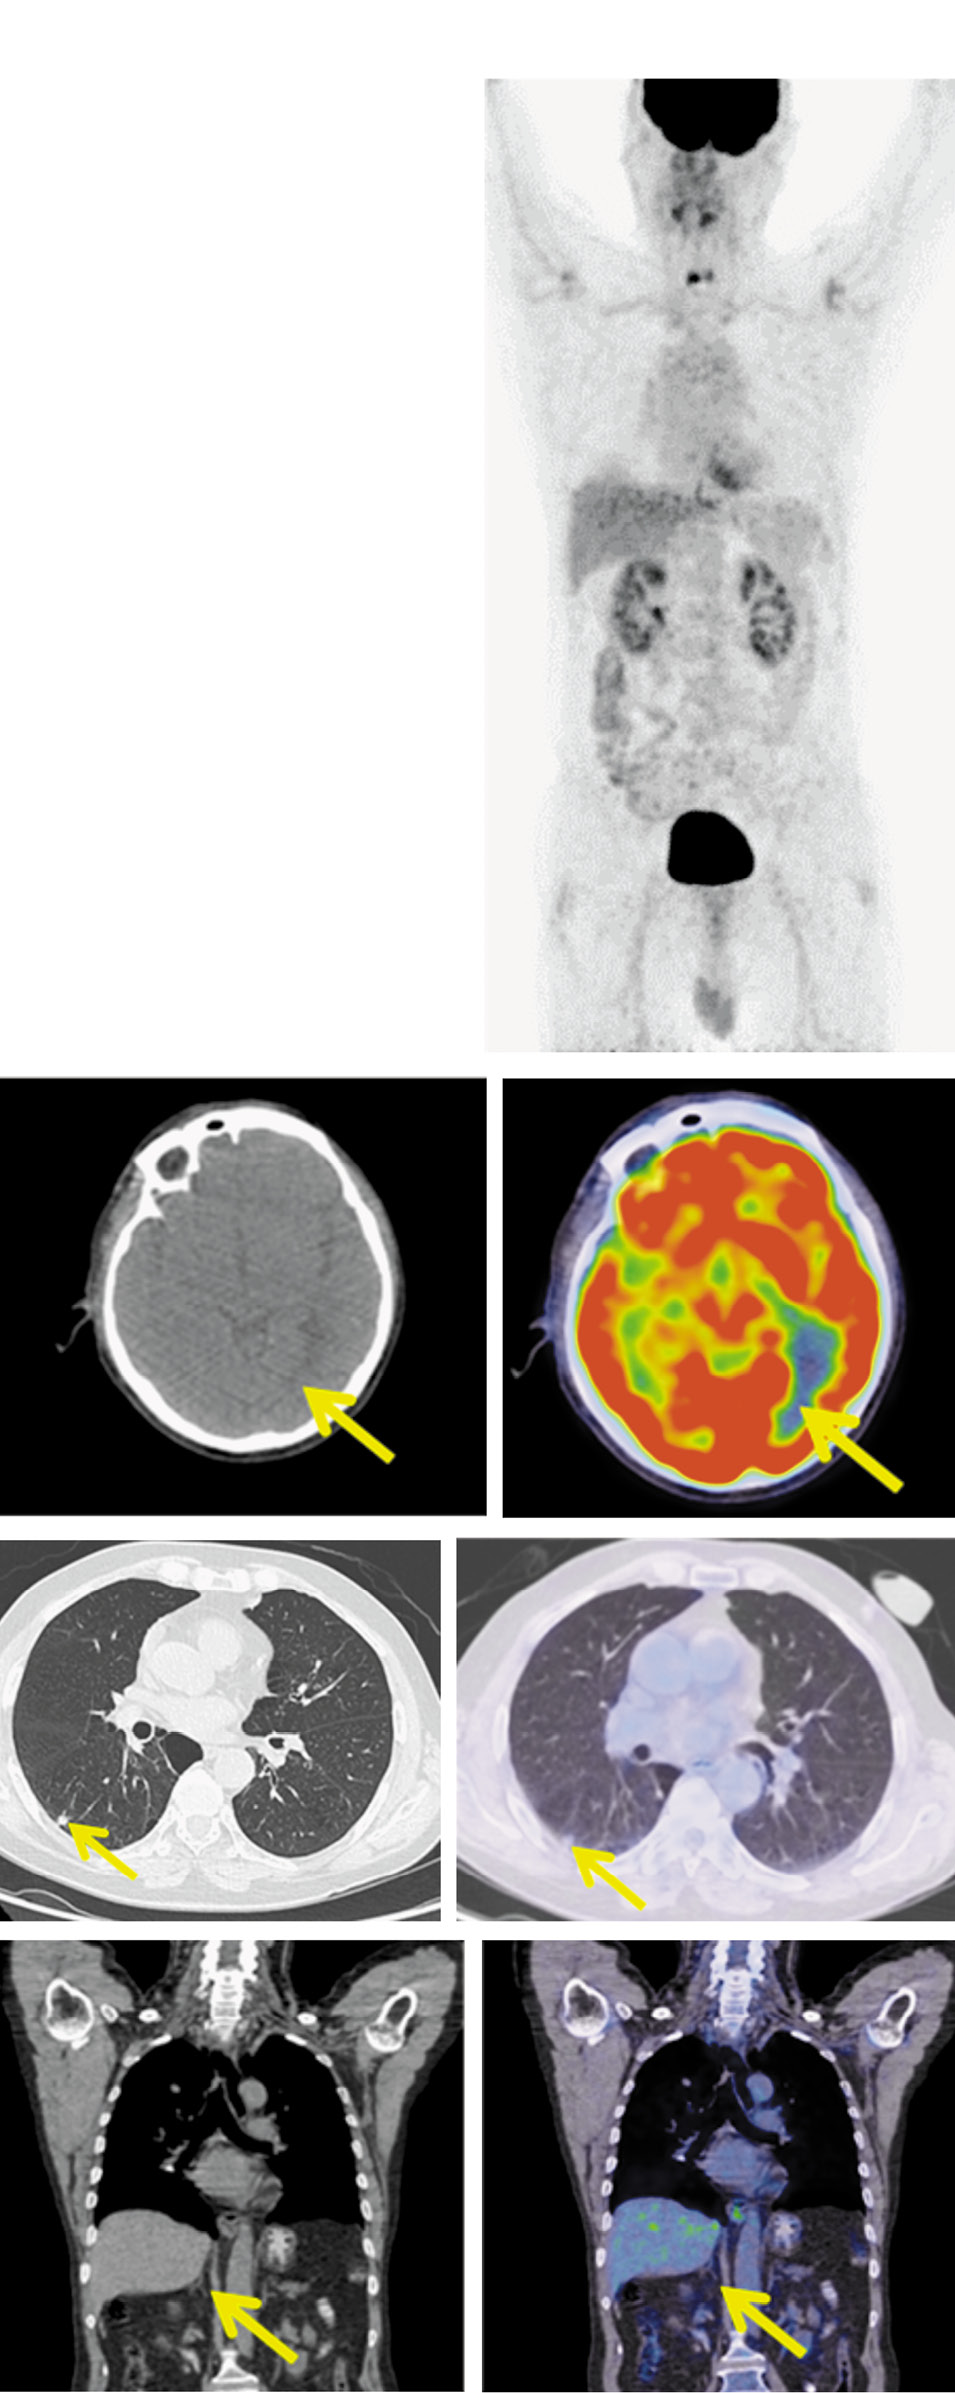

Рис. 4. Пациент Н.,64 года. После 14 циклов терапии. На MIP, аксиальной и корональной КТ и ПЭТ/КТ-проекциях в левой затылочной доле очагов фиксации РФП нет. Лимфатические узлы шеи не увеличены, метаболически не активны. В субплевральном отделе S6 правого легкого сохраняется образование размером до 9 мм, без метаболической активности ФДГ. В задневерхнем средостении паратрахеально справа уплотнение клетчатки без четких контуров, размером 16×13×10 мм без метаболической активности. ФДГ, медиастинальные лимфоузлы не увеличены. Образование в правом надпочечнике регрессировало.

Fig. 4. A 64-year-old patient N. The condition of the patient after 12 cycles of therapy. MIP, axial and coronal CT and PET/CT images show the left occipital lobe without increased uptake of radiopharmaceutical. Cervical lymph nodes are not enlarged and without metabolic activity. The lesion measuring 9 mm, without increased RFP uptake is still detected in the subpleural section of the right lung S6 segment. In the posterosuperior mediastinum in the right paratracheal space a fiber compaction with poorly defined boundaries, measuring 16×13×10 mm without RFP uptake is detected, the mediastinal lymph nodes are not enlarged. The lesion on the right adrenal gland has regressed.

Для оценки эффекта проводимой терапии 26.02.2020, после 14 циклов, выполнена ПЭТ/КТ с 18-ФДГ. В левой затылочной доле очагов фиксации РФП нет. Лимфатические узлы шеи не увеличены, метаболически не активны.

В субплевральном отделе S6 правого легкого сохраняется образование размером до 9 мм без метаболической активности ФДГ.

В задневерхнем средостении паратрахеально справа имеется уплотнение клетчатки без четких контуров, сливающееся с правой стенкой пищевода, размером до 16×13×10 мм без метаболической активности ФДГ, медиастинальные лимфатические узлы не увеличены.

Образование в правом надпочечнике не определяется (рис. 4). По критериям RECIST (Response Evaluation Criteria in Solid Tumors ) v.1.1 получена полная метаболическая регрессия.